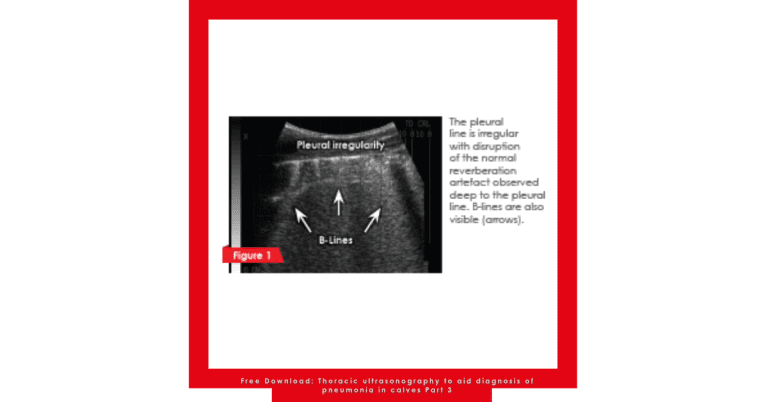

Free Download: Thoracic ultrasonography to aid diagnosis of pneumonia in calves Part 3

Bovine respiratory disease (BRD) is highly prevalent amongst dairy and beef heifers. It is the main cause of death in both Holstein dairy calves over 30 days of age and in milk-fed calves. Early diagnosis of BRD must be a priority for the farm and veterinarian. When identified quickly, the risks of irreversible lung damage and long-term effects are reduced, therapeutic success of antimicrobials is maximised, antimicrobial resistance is minimised and recurrence rates are lowered.